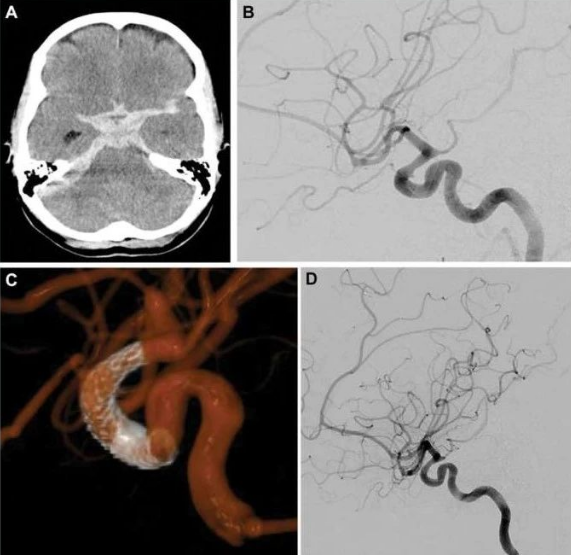

密网支架是为复杂、难治性动脉瘤而生的,因此早期的适应证也主要限定于:难治性夹层、大型及巨大型动脉瘤,表现为颈内动脉大型及巨大型动脉瘤的闭塞率较高,相比于其他方法更有优势。不过随着其广泛应用,发现它较以前的单纯栓塞、支架辅助栓塞更安全有效,因此其适应症逐步拓宽,在破裂动脉瘤、小型及中型动脉瘤、后循环动脉瘤、Willis环远端动脉瘤、儿童患者等领域开始应用。

(5)破裂动脉瘤和血泡样动脉瘤有文献报道的成功经验,可以慎重选用FD治疗。如果动脉瘤形态和条件允许,急性期先行弹簧圈填塞,二期行FD置入也是较好的治疗方案。

从密网支架的应用看起来,PED在全球应用已经超过10万例,相关研究的中英文文献有600余篇,其动脉瘤总体的1年完全闭塞率可以达到85.5%,总体并发症发生率为7.1%。并发症主要包括:技术相关性并发症、出血性相关并发症、缺血性相关并发症、载瘤动脉分支或穿支闭塞占位效应。这些并发症正在通过技术的改进提高、器械的优化、适应证的选择而逐渐降低。